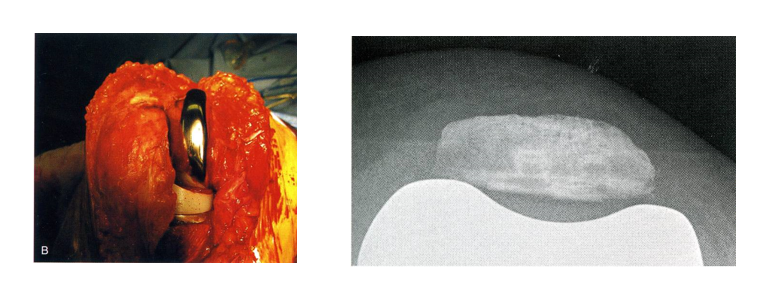

正常髌骨轨迹

下肢残留外翻畸形

股骨假体外翻放置

髌骨高位

假体几何形状不良,解剖型

滑车翼易与髌骨匹配

假体选择